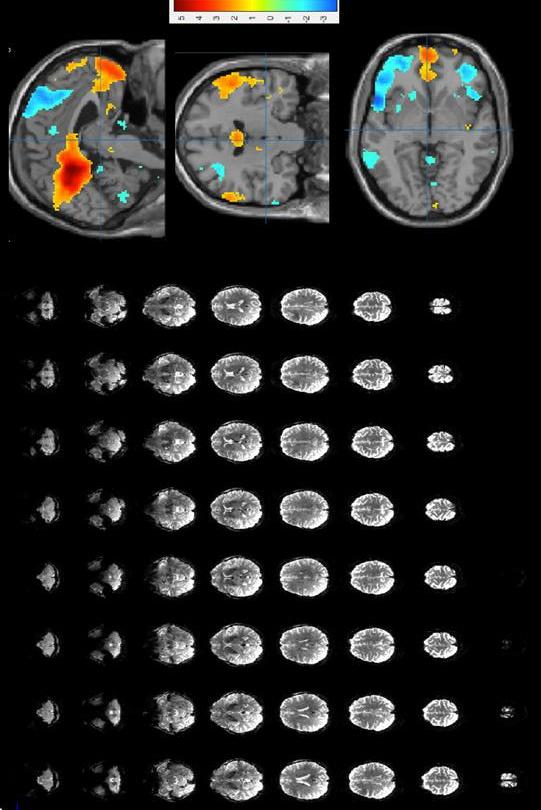

Finger tapping task: activation of motor and visual cortex

b )

b) Resting state MRI: activation in the default network Resting state MRI: activation in the default mode network

Fig. 7: In a), post-processed finger tapping task acquired at 1.5mm iso, TR = 2.5 seconds, 3 min total acquisition time. In b), post-processed resting stated functional MRI, acquired at 2mm isotropic, TR = 1s, 6 min total acquisition time.

Fig. 6: In a), post-processed finger tapping task acquired at 1.5mm isotropic resolution, TR = 2.5 seconds, 3 min total acquisition time, 1 subject. In b), post-processed resting state functional MRI, acquired at 2mm isotropic resolution, TR = 1s, 8 min total acquisition time, 1 subject.